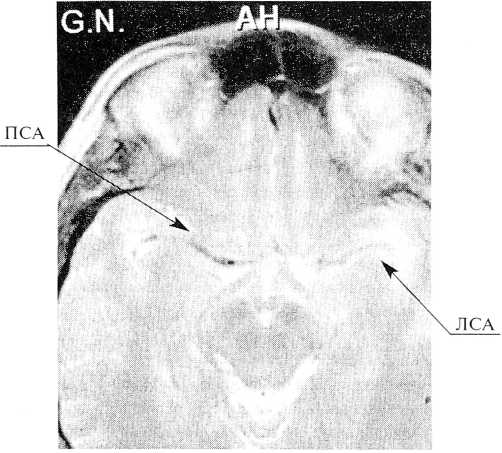

Состояние прогрессивно ухудшалось и больная переведена в клинику нейрохирургии, где через 4 часа после случившегося начата операция — селективная церебральная ангиография, реканализация левой внутренней сонной артерии (ВСА). После пункции правой бедренной артерии и катетеризации ее интродьюсером 4F, катетер проведен в левую общую сонную артерию (ОСА). Ангиография в прямой и боковой проекциях. Выявлена окклюзия ВСА, контрастировалась только проксимальная ее часть. Катетеризирована правая ВСА. Ангиография в прямой, боковой, косых проекциях. Обе передние мозговые артерии (ПМА) А2 контрастировались из правого каротидного бассейна, левая ПМА А1 не визуализировалась. Катетеризирована левая ПА. Ангиография в прямой и боковой проекциях. Визуализировалась левая задняя соединительная артерия (ЗСоА), в левую ВСА контраст не поступал. Таким образом, ангиографически имелись признаки тромбоза левой ВСА от уровня ниже глазничной артерии, дистально зона тромбоза достигала по меньшей мере бифуркации ВСА (рис. 2—5).

Рис. 2—3. Больная В., дигитальная субтракционная ангиограмма (боковая проекция).

Визуализируются левая ОСА, НСА. Левая ВСА контрастируется в проксимальной части

Рис. 4—5. Больная В., дигитальная субтракционная ангиограмма (прямая проекция, рис. 4) и (косая проекция, рис. 5).

Визуализируется правая ВСА и ее интракраниальные ветви. Данных за нарушение проходимости магистральных сосудов не получено